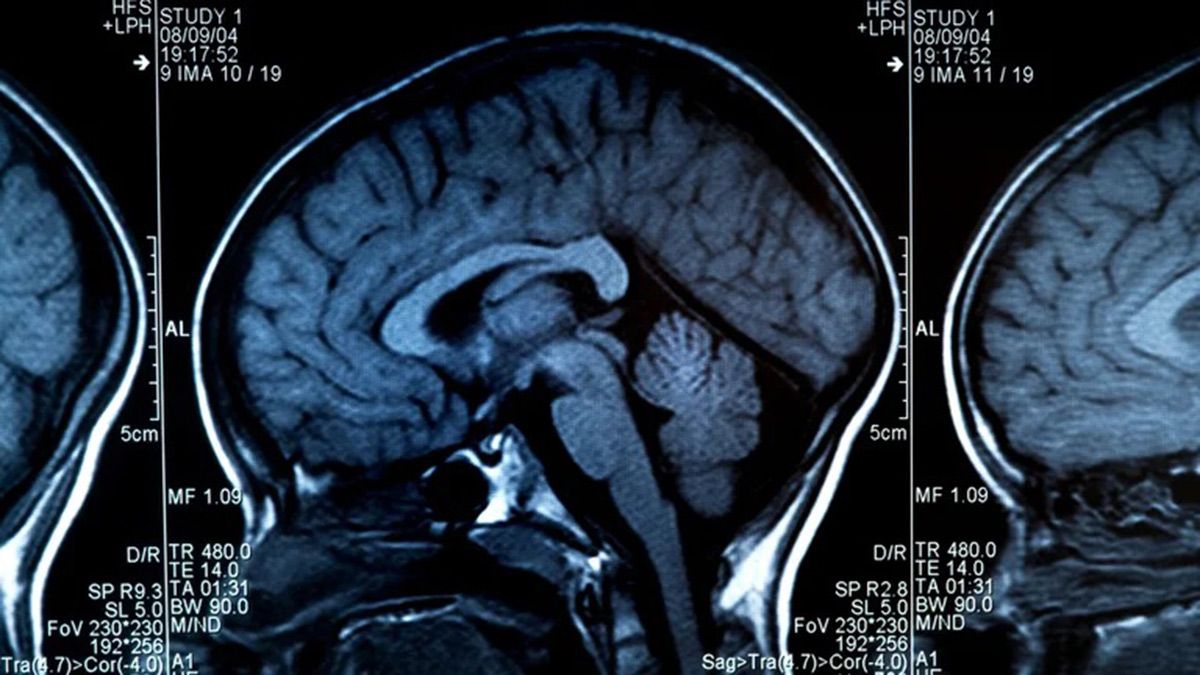

El envejecimiento conlleva muchos cambios físicos, biológicos, químicos y psicológicos, y el cerebro no es una excepción a este fenómeno. Estos diversos cambios han intentado ser cartografiados por modelos conceptuales como la Teoría del Andamiaje del Envejecimiento y la Cognición (STAC) en 2009. El modelo STAC tiene en cuenta factores como los cambios neuronales en la sustancia blanca, el agotamiento de la dopamina, el encogimiento y el adelgazamiento cortical.[5] Las tomografías computarizadas han revelado que los ventrículos cerebrales se dilatan con la edad. Estudios de IRM más recientes han informado de disminuciones regionales del volumen cerebral relacionadas con la edad.[6][7]La reducción del volumen regional no es uniforme; algunas regiones cerebrales se encogen a un ritmo de hasta el 1% anual, mientras que otras permanecen relativamente estables hasta el final de la vida.[8]El cerebro es muy complejo y está compuesto por muchas zonas y tipos de tejido o materia diferentes. Las diferentes funciones de los distintos tejidos del cerebro pueden ser más o menos susceptibles a los cambios inducidos por la edad.[6]La materia cerebral puede clasificarse en materia gris o materia blanca. La materia gris está formada por los cuerpos celulares de la corteza y los núcleos subcorticales. La materia blanca está formada por axones mielinizados densamente empaquetados que conectan las neuronas entre sí y con la periferia.[6]

Los avances en la tecnología de resonancia magnética han proporcionado la capacidad de ver la estructura cerebral con gran detalle de forma fácil y no invasiva in vivo. Bartzokis et al., han observado que el volumen de materia gris disminuye entre la edad adulta y la vejez, mientras que el volumen de materia blanca aumenta a partir de los 19-40 años y disminuye después de esa edad.[13]Los estudios que utilizan la morfometría basada en vóxeles han identificado zonas como la ínsula y el giro parietal superior como especialmente vulnerables a las pérdidas de materia gris relacionadas con la edad en los adultos mayores.[13] Sowell et al., informaron de que las primeras 6 décadas de la vida de un individuo se correlacionaban con las disminuciones más rápidas de la densidad de materia gris, y esto ocurría en los lóbulos dorsal, frontal y parietal, tanto en las superficies cerebrales interhemisféricas como en las laterales. También cabe destacar que zonas como el giro cingulado y el córtex occipital que rodea el surco calcarino parecen estar exentas de esta disminución de la densidad de materia gris con el paso del tiempo.[13]Los efectos de la edad sobre la densidad de materia gris en el córtex temporal posterior aparecen de forma más predominante en el hemisferio izquierdo que en el derecho, y se limitaron a los córtex posteriores del lenguaje. Algunas funciones del lenguaje, como la recuperación y producción de palabras, se localizan en las cortezas lingüísticas más anteriores y se deterioran con la edad. Sowell et al. también informaron de que estas cortezas lingüísticas anteriores maduraban y se deterioraban antes que las cortezas lingüísticas posteriores.[13]También se ha observado que la anchura del surco no sólo aumenta con la edad,[14]sino también con el deterioro cognitivo en los ancianos.[15]